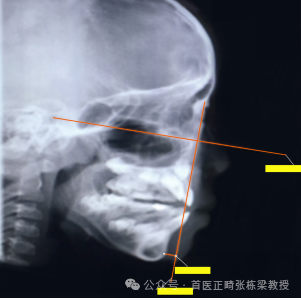

我们会给孩子拍X光片,设定FH平面,找出眶点、耳点、鼻根点,从鼻根点向下做垂线,分析上颌骨的A点和下颌骨的颏前点距离,这条线的距离,是我判断地包天骨骼问题,比较常用的方法。